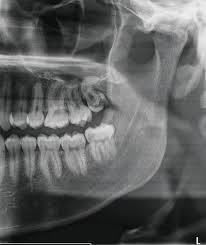

We provide Panoramic dental x-ray services which use a very small dose of ionizing radiation to capture the entire mouth in one image. It is commonly performed by dentists and oral surgeons in everyday practice and may be used to plan treatment for dentures, braces, extractions, and implants.